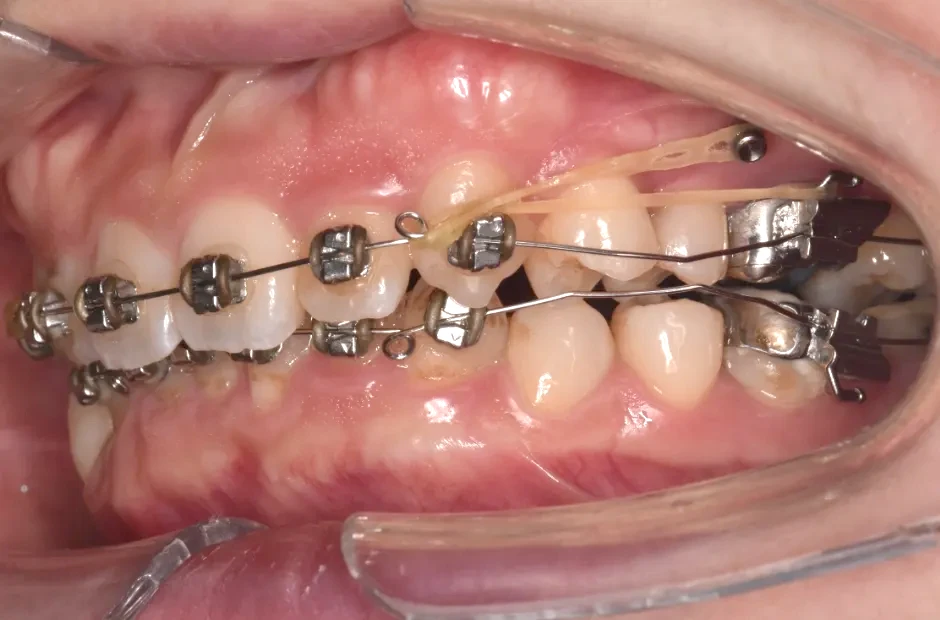

治療中